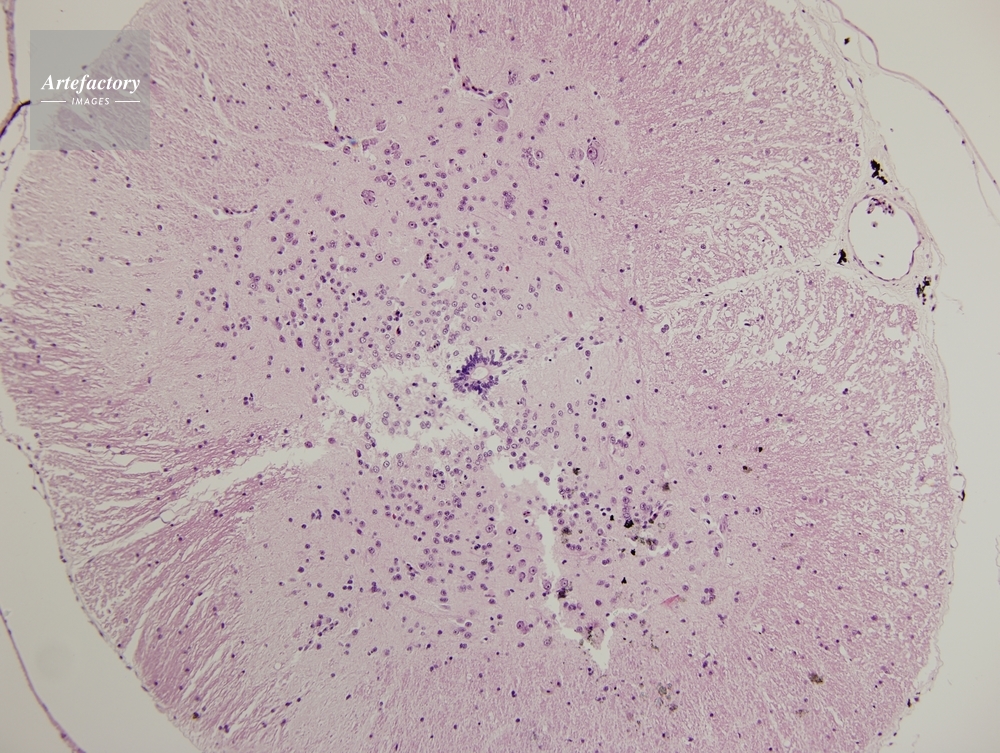

| 作品タイトル | ウシガエル,脊髄 | モデルリリース | なし | |